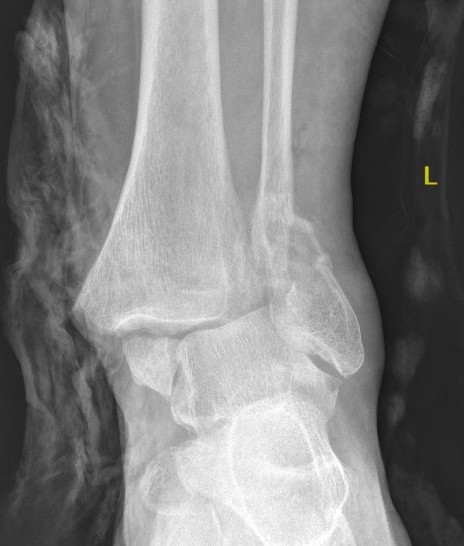

Issues

Poor bone

Poor skin

Poor wound healing

Poor union rates

ORIF

- poor bone stock

- wound issues